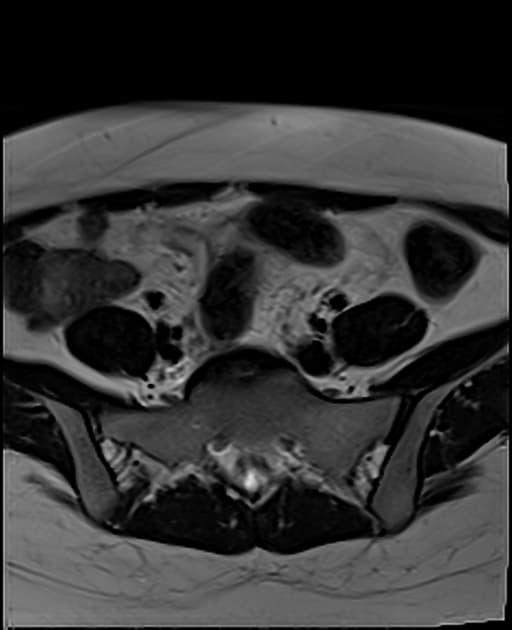

Series (14)

Axial C+ portal venous phase

- Điểm chuyển tiếp không rõ giới hạn (ill-defined transition point) tương tự ở vùng chậu, liên quan đến tăng dày và tăng quang thành ruột (bowel wall thickening and enhancement).

- Tăng dày và tăng quang rõ rệt một đoạn ruột non ở vùng phụ tạng phải/vùng sau tử cung (right adnexal/retrouterine region).

- Một vài ổ nhỏ tín hiệu tăng trên T1 (T1 hyperintense foci) ở cả hai vùng phụ tạng (adnexal regions), gợi ý các ổ lạc nội mạc tử cung (endometriotic deposits).